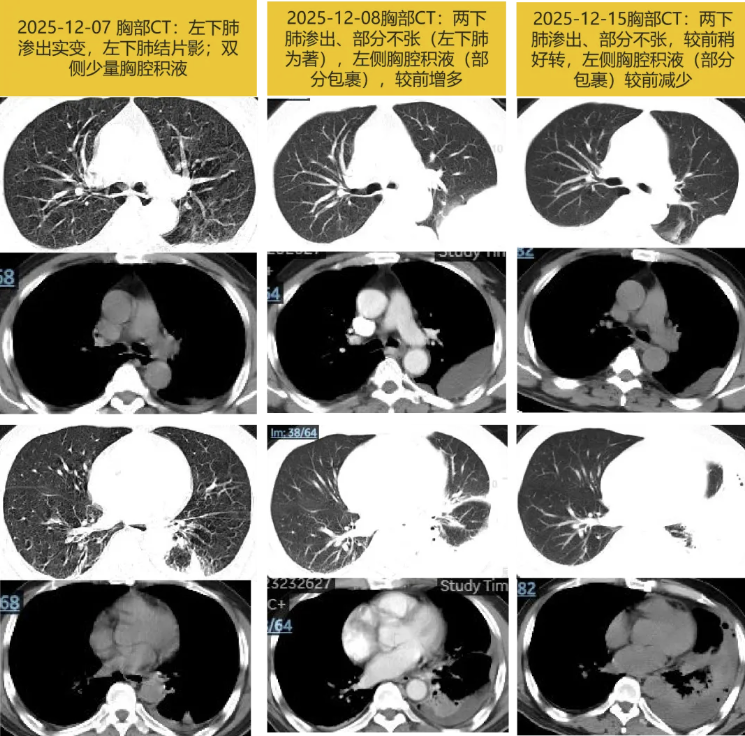

2025-12-01 受凉后出现咳嗽咳白痰,伴流涕,无发热寒战、胸闷气急、腹痛腹泻等,未重视未诊治。症状逐渐增加,并出现活动后气急,2025-12-07晨出现心前区疼痛,呼吸及咳嗽时疼痛明显,痰中带血丝,当地急诊测指尖氧饱和度(不吸氧)95%;查WBC 15.12×10^9/L,N 81.2%;CRP 62.6mg/L,PCT 0.1ng/mL;D-二聚体 0.53mg/L,cTnT 0.008ng/mL。心电图:窦性心动过速。胸部平扫CT: 左下肺渗出实变,左下肺结片影,炎性灶可能大;双侧少量胸腔积液,肺气肿。予左氧氟沙星0.5g qd抗感染,好转不明显。

2025-12-08 入住某三甲医院急诊科,查WBC 12.36×10^9/L,N 81.6%;降钙素原:31.9ng/mL,CRP 203.5mg/L;胸部增强CT: 两下肺渗出、部分不张(左下肺为著),较前25-12-07片进展,左侧胸腔积液(部分包裹),较前增多。2025-12-09 超声引导下行胸腔穿刺置管引流,引出黄色浑浊液体。胸水常规:红细胞 5200/mm3,白细胞 14223/mm3,多个核细胞 87%,单个核细胞 11%,嗜酸性粒细胞 2%;胸水涂片找细菌、真菌、抗酸杆菌阴性,细菌培养阴性。予左氧氟沙星0.5g qd(12-08至12-11)抗感染,胸痛、咳嗽咳痰好转。

2025-12-14 床旁超声见胸水量少,予拔出胸腔引流管。复查WBC 6.53×10^9/L,N 70.9%;CRP 110.5mg/L,PCT 0.64ng/mL;较前下降。胸部平扫CT:两下肺渗出、部分不张(左下肺为著),较前2025-12-08片稍好转,左侧胸腔积液(部分包裹)较前稍减少,其内新增少量积气,改莫西沙星0.4g qd静脉滴注。12-16予莫西沙星0.4g qd口服出院。